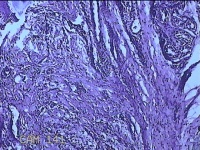

右侧手掌肉芽组织

性别

女

年龄

48岁

临床诊断

手掌开放性损伤

一般病史

右侧手掌肉芽组织增生

标本名称

大体所见

灰白暗红色带皮肤样组织1.3x0.8x0.3cm一块,切面灰白粉红色,质软。

图1